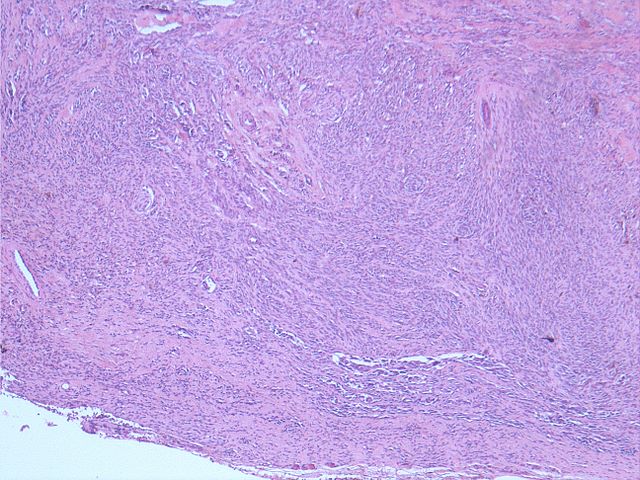

610 -- image8.jpg